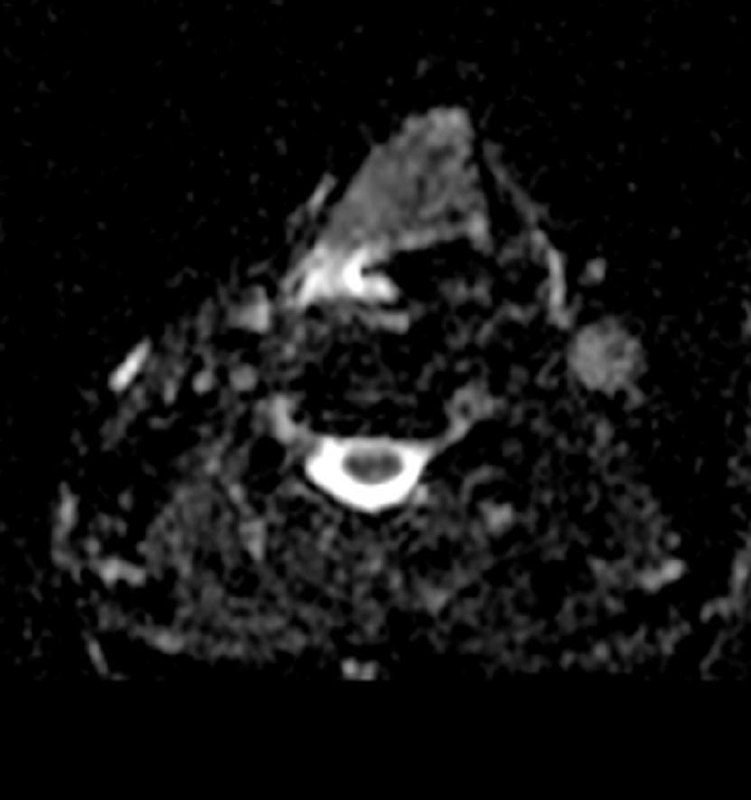

Всем привет!

А вот для чего иногда нужен контраст на МРТ предстательной железы: по DWI, а она является основной последовательностью для оценки периферической зоны, типичные изменения ПИРАЦ-4 (наибольший размер - 12 мм), но вот на Т2 - жидкость, а не серость, и на постконтрастных накопления контраста нет вообще. Так что, это - абсцесс, а не рак.

Соблюдайте протокол и не будете разочарованы.